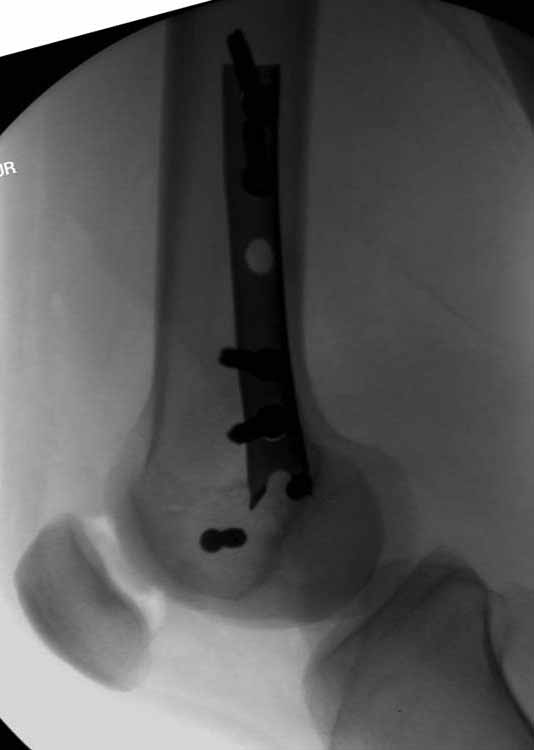

Здесь пример медиальной пластины и латеральный комбинированный метод (у второго больного старый перелом тибиал плато, леченный где то и когда то)

Пластину надо устанавливать на апексе перелома, иначе фрагмент начнет сползать. А на второй стороне, если имеется большой одиночный фрагмент тогда проблем не бывает, и их можно собрать компрессирующими винтами. Проблема наступает тогда когда многофрагментраность на латеральной стороне, где надо применить комбинированный метод, иногда несколькими пластинами. Или сменой позиции установки пластины, чтобы максимально прикрыть перелом и создать боковую поддержку.

Случаи могут быть разными и варианты фиксации могут быть различными. Это не эталон фиксации, и не каждый метод является "золотым стандартом". А “золотым” считается, когда внутрисуставной перелом отрепонирован на отлично и зафиксирован адекватно. Если возможно закрыто - хорошо, а так не надо искать только легкий закрытый путь, зная анатомию можно открывать, сколько надо!